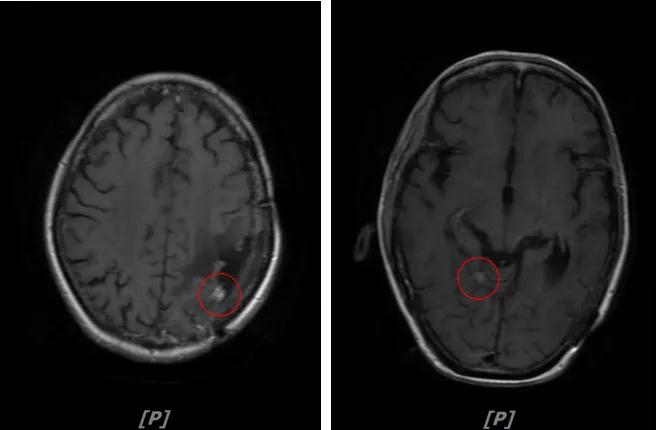

5. 病情第4次进展:2019年11月患者出现视野模糊等症状

头颅增强MR:左侧顶颞叶见片状T1WI低信号、T2WI高信号影,病灶大部信号接近脑脊液,增强后术区边缘左侧顶叶见结节状强化影,大小约10x8x11mm,较2019-03- 15MR老片大致相仿;右侧脑室三角区见结节样T1WI等低信号、T2WI不均匀稍高信号影,增强后不均匀明显强化,大小约24x18x20mm,较2019-03-15MR老片明显增大;两侧半卵圆区、侧脑室旁见较对称片状T1WI低信号、T2WI高信号影,增强后未见明显强化,较前片相仿;余脑室、脑池、脑沟大小形态可,中线结构向左偏移。

左顶颞叶转移瘤治疗后改变

右侧脑室三角区旁强化结节,较2019-03-15MR老片明显增大 左侧顶叶强化结节,较2019-03-15MR老片大致相仿

两侧脑室旁云絮状异常信号,考虑放疗后改变

患者三线治疗的PFS为14个月,2019年12月给四线治疗为“吡咯替尼+阿那曲唑”基础上联合曲妥珠单抗。

患者视野模糊等症状有所改善,继续定期复查。